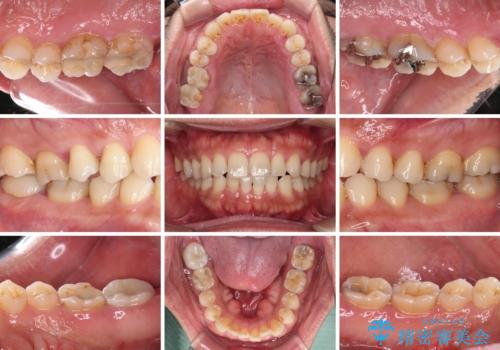

- 奥歯の間から出血するとのことで来院された患者様です。

口腔内は非常にきれいで、定期的に歯科医院でのクリーニングも行っているとのことでしたが、歯肉からの出血が一向に解決しない状態でした。

奥歯の歯間部の歯肉が炎症で赤黒くなっており、歯周ポケットを検査したところ、6-8mm(正常では3mm以下)であり、外科処置が適用となる状態でした。

まずは仮歯に置き換え、歯周ポケットを除去するための外科処置(歯肉弁根尖側移動術)を行い、治癒を待ってセラミッククラウンにて補綴治療を行うこととしました。